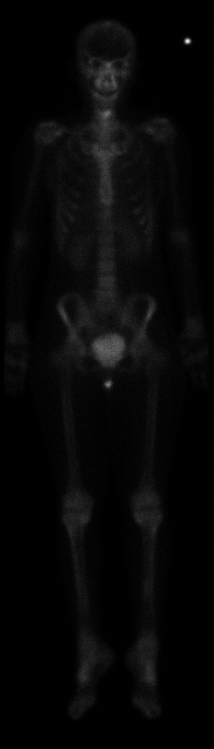

When a pain starts,and doesn't go away....after awhile you know something's wrong and then you submit to the testing. The technician running the bone scan said "{pause} good luck with everything," my husband calling with the report he picked up "{pause} it's not good..." my oncologist calling after my husband called about what to do next "I wish I had good news, but I need more pictures to see what's going on..." and the wording from the bone scan results all add up. It is no good. MRI tomorrow....I think it's time to make plans to travel the world before this thing does me in. Here are my bone scan pictures (not high quality, but you can see the brightness on the neck).

Front: